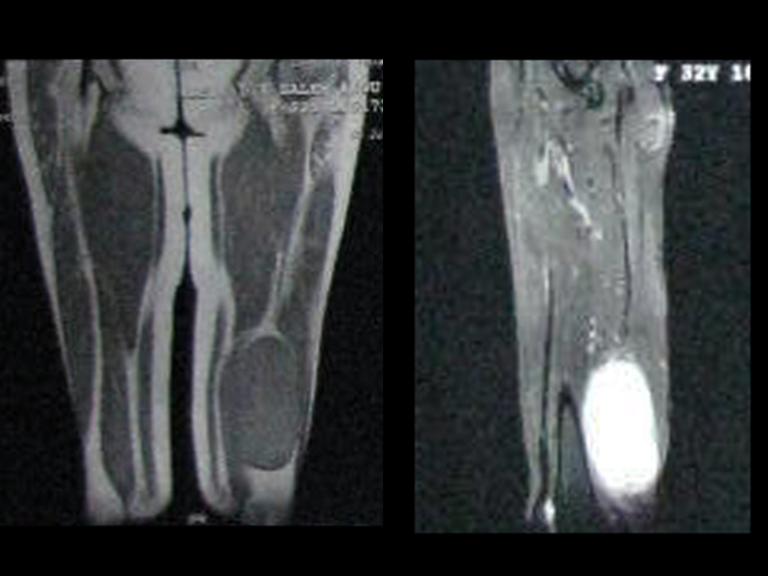

As lesões ósseas que mais freqüentemente dão manifestações clínicas, necessitando de cirurgia ortopédica, ocorrem no fêmur, úmero, vértebras, pelve, escápula e tíbia, nesta ordem.

A história natural desta afecção cursa com dor e geralmente o diagnóstico pode ocorrer devido a fratura em osso patológico que causa impotência funcional, limitação para as atividades da vida diária, dependência de terceiros, escaras e falência de múltiplos órgãos devido ao paciente estar acamado.

A atuação do ortopedista oncológico visa operar a lesão metastática o mais precoce possível visando aliviar a dor, restabelecer a função e melhorar a qualidade de vida do paciente.

Para isto são realizadas cirurgias de ressecção e reconstrução com osteossíntes com cimento ou endopróteses.